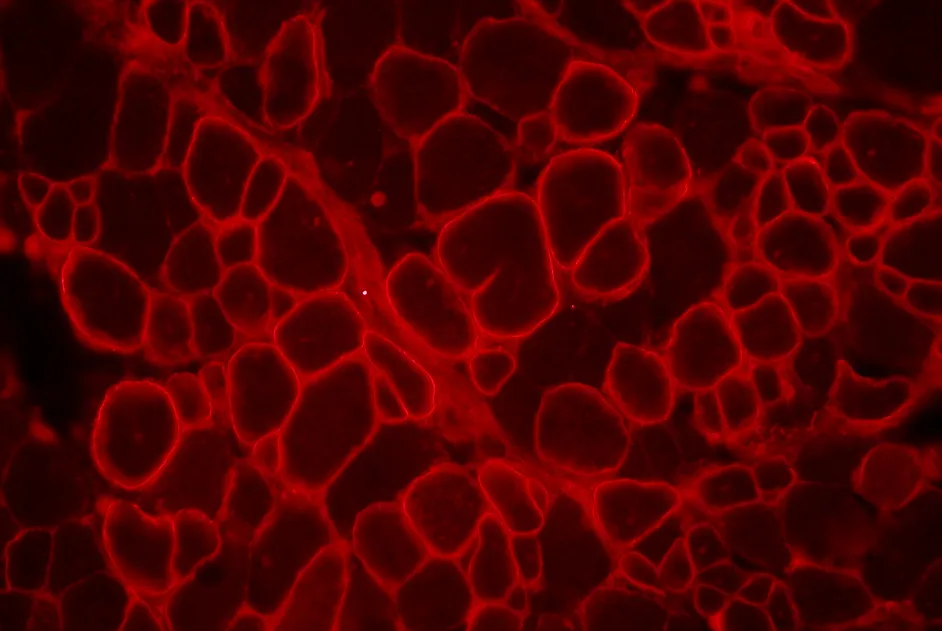

Une nouvelle étude, soutenue par l’AFM-Téléthon, montre que la restauration par thérapie génique de SMN uniquement dans les motoneurones de souris n’est pas suffisante.